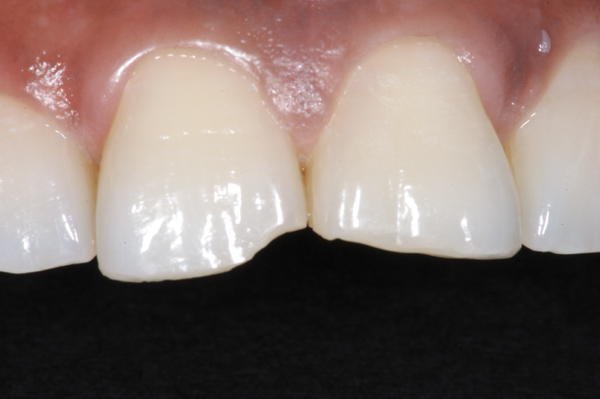

Fig 8. Esthetic restoration of the fractured maxillary central incisors using an etch-and-rinse adhesive with a nanohybrid composite resin.

Figure 8